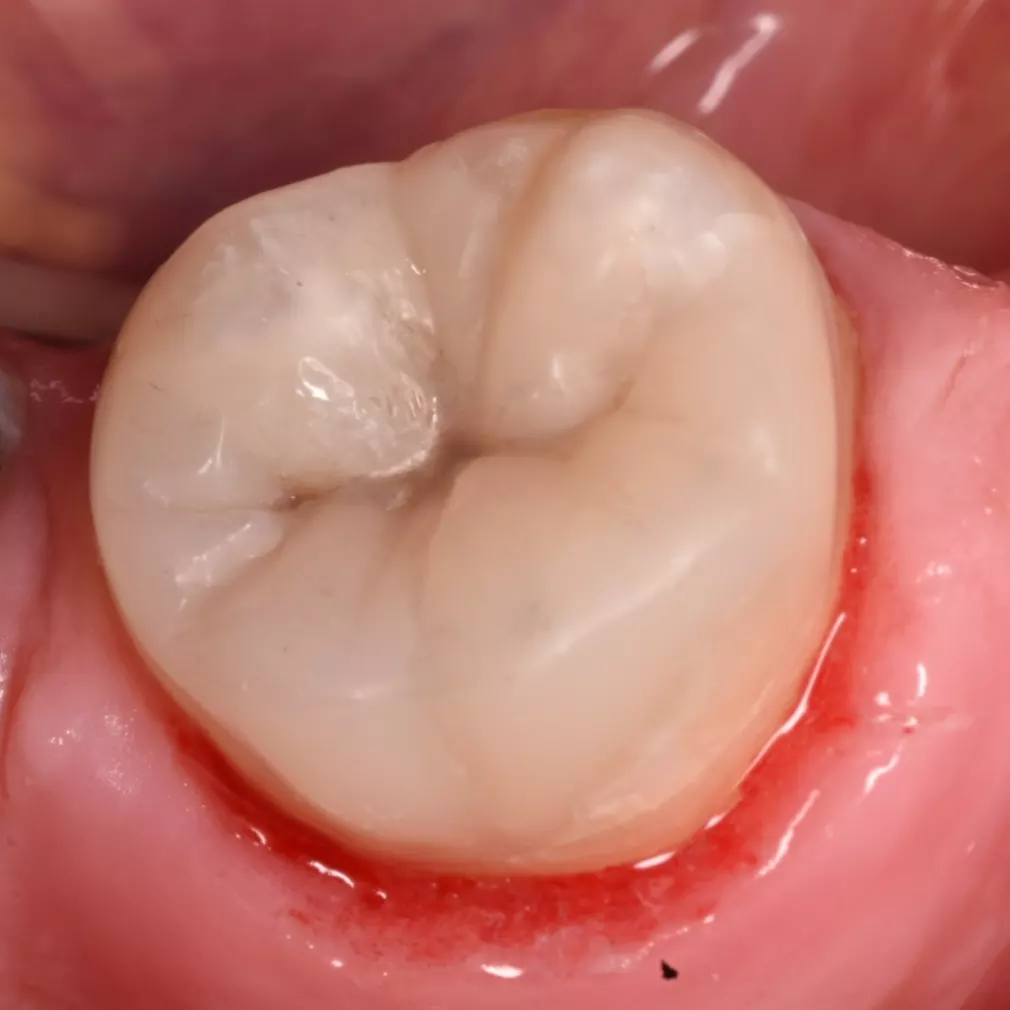

Checking high spots

After removing a slight high spot that present

Final result after finishing and polishing